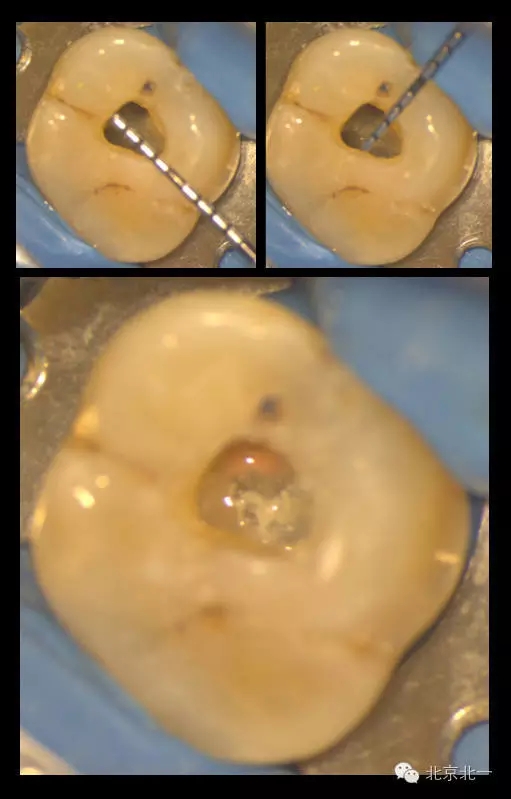

在我們看來,微創(chuàng)的入路設(shè)計是需要條件限制的。首要條件就是在入路開放后醫(yī)師能明確牙齒內(nèi)根管的分布與走行。醫(yī)師或者在術(shù)前通過CBCT明確根管解剖行程,或者能夠從開髓入口處檢視到髓底的全部區(qū)域以防遺漏根管。

下圖是我們研究生小苑的課題,在顯微CT的輔助下,借助牙面標記點進行髓腔入路的設(shè)計:根據(jù)CT數(shù)據(jù)建立的根管模型,將每個根管的延長線投影至牙冠表面,連接各表面投影點后即為開髓的通道。這樣的開髓入路下,既暴露出了所有根管口,從不同的視角方向下也能看到完整的髓底解剖。

再看我們的現(xiàn)實,在我們的日常工作中,也一直期望能對微創(chuàng)開髓多有嘗試,可惜的是由于我國患者的口腔保健意識還有待提高,很多來牙髓病??凭驮\的患者牙體本身由于病變已沒有微創(chuàng)的可能。前段時間終于等到了這么一例牙周牙髓聯(lián)合病變,患者有著強烈的保留牙齒的愿望,但在牙周治療中并發(fā)了牙髓炎的癥狀,因此轉(zhuǎn)診至牙體牙髓專科需要進行根管治療。

對于這個冠部牙體組織完好的病例,我們也確實想給她盡量保留健康組織,于是就開始了對這個病例的微創(chuàng)治療。